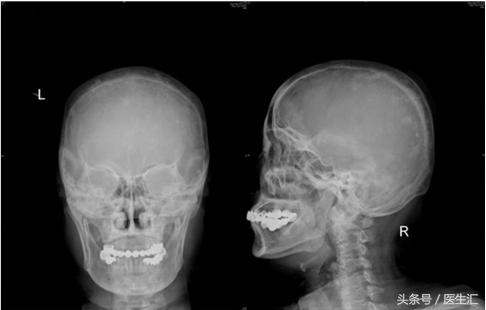

X线片:颅骨弥漫性病变(斑点状骨致密影),胸椎未见明显骨质异常,腰椎退行性变,骶尾椎轻度退变,双髋轻度退变,双膝关节轻度退变;

头颅正侧位X线片

(1)颅骨X线:颅骨弥漫性病变(斑点状骨致密影);